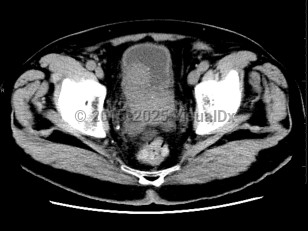

Prostate cancer

Most prostate cancers are identified at the local stage through annual screenings, and the majority of patients are asymptomatic at that stage. At later stages, physical findings may include perineal pain and urinary changes (eg, frequency, retention, nocturia). Urinary changes in men are more frequently the result of benign prostate conditions, which are sometimes found as comorbidities. Physical examination may reveal areas of induration, asymmetry, and/or prostate nodule. Diagnosis is confirmed via prostate biopsy.

If cancer has spread, physical findings may include bone pain or pathologic fracture. See metastatic prostate carcinoma.